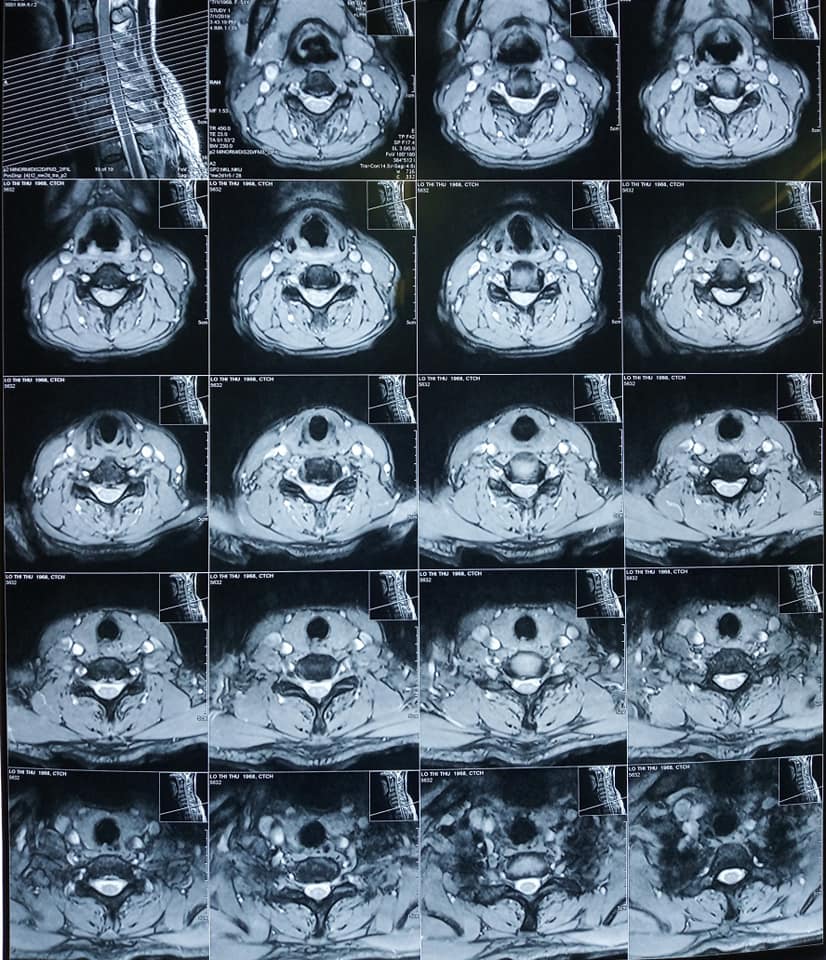

Bệnh nhân Lô Thị Thư ở Nghĩa Đàn, Nghệ An được chuyển tuyến đến Bệnh viện Chấn thương Chỉnh hình Nghệ An trong tình trạng sức khỏe yếu, đau đầu nhiều, sưng nề vùng mặt, đau hạn chế vận động cột sống cổ, tê bì hai tay, không ngồi dậy được.

Sau khi được bác sĩ thăm khám, bệnh nhân được chẩn đoán bị Thasit vị đĩa đệm cột sống cổ C4C5 C5C6 và  phù tủy cổ ngang mức C5.

Hình ảnh Phim chụp tình trạng :